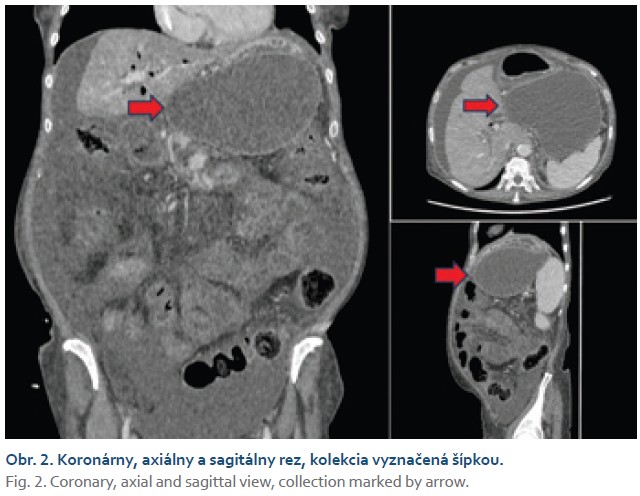

Na upresnenie nálezu sa realizovalo kontrastné CT, ktoré zobrazilo objemnú cystickú expanziu v oblasti veľkej kurvatúry žalúdka o veľkosti 127 × 142 × 86,5 mm, tiahnucu sa až po pylorus, ktorá podmieňovala kompresiu žalúdka (obr. 2), vedľajším nálezom bola karcinomatóza peritonea. Nakoľko pacientka neprekonala akútnu pankreatitídu, ani sa neliečila na chronickú pankreatitídu, kolekciu sme považovali za ohraničený paramalígny ascites, a to aj na základe novozistenej karcinomatózy peritonea a absenciu inej možnej príčiny. V snahe o zlepšenie kvality života pri paliatívnej starostlivosti sa po získaní informovaného súhlasu uprednostnila transgastrická drenáž pomocou endoskopickej ultrasonografie (EUS) pred zavedením perkutánneho drénu.